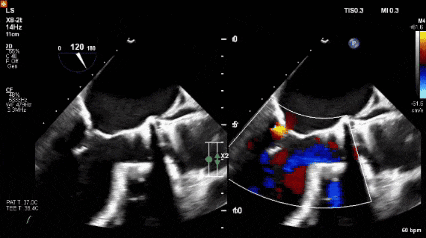

首次TAVR后并发完全性房室传导阻滞,LVEF仅29%,植入双心室起搏器。既往合并高血压。本次入院经胸超声提示 Evolut R 瓣膜瓣上瓣叶增厚并严重钙化(图1,视频1),峰值流速3.9m/s,平均压差33mmHg,有效瓣口面积0.67cm²。TEE 显示重度生物瓣狭窄、重度跨瓣反流及轻度瓣周漏(图2,视频2)。左心耳血栓大小2.9×1.0cm。

图2经食道超声心动图显示的左心室流出道视图

可见严重的跨瓣膜反流(白色箭头),以及轻微的瓣周反流(白色箭头)。

随后采用23 mm TRUE 球囊对未完全扩张的 S3UR 瓣膜行后扩张(图6D,视频9)。后TEE提示瓣膜位置良好,无瓣周漏(PVL)。

术后第1天TTE显示左室射血分数40%,无跨瓣反流,轻微瓣周漏,平均跨瓣压差6mmHg,有效瓣口面积1.78 cm²。术后恢复顺利,于术后第11天出院。

30天随访时患者NYHA Ⅱ级。TTE显示峰值流速1.5 m/s,平均压差6mmHg,有效瓣口面积1.43cm²,无跨瓣反流,仅轻度瓣周漏。